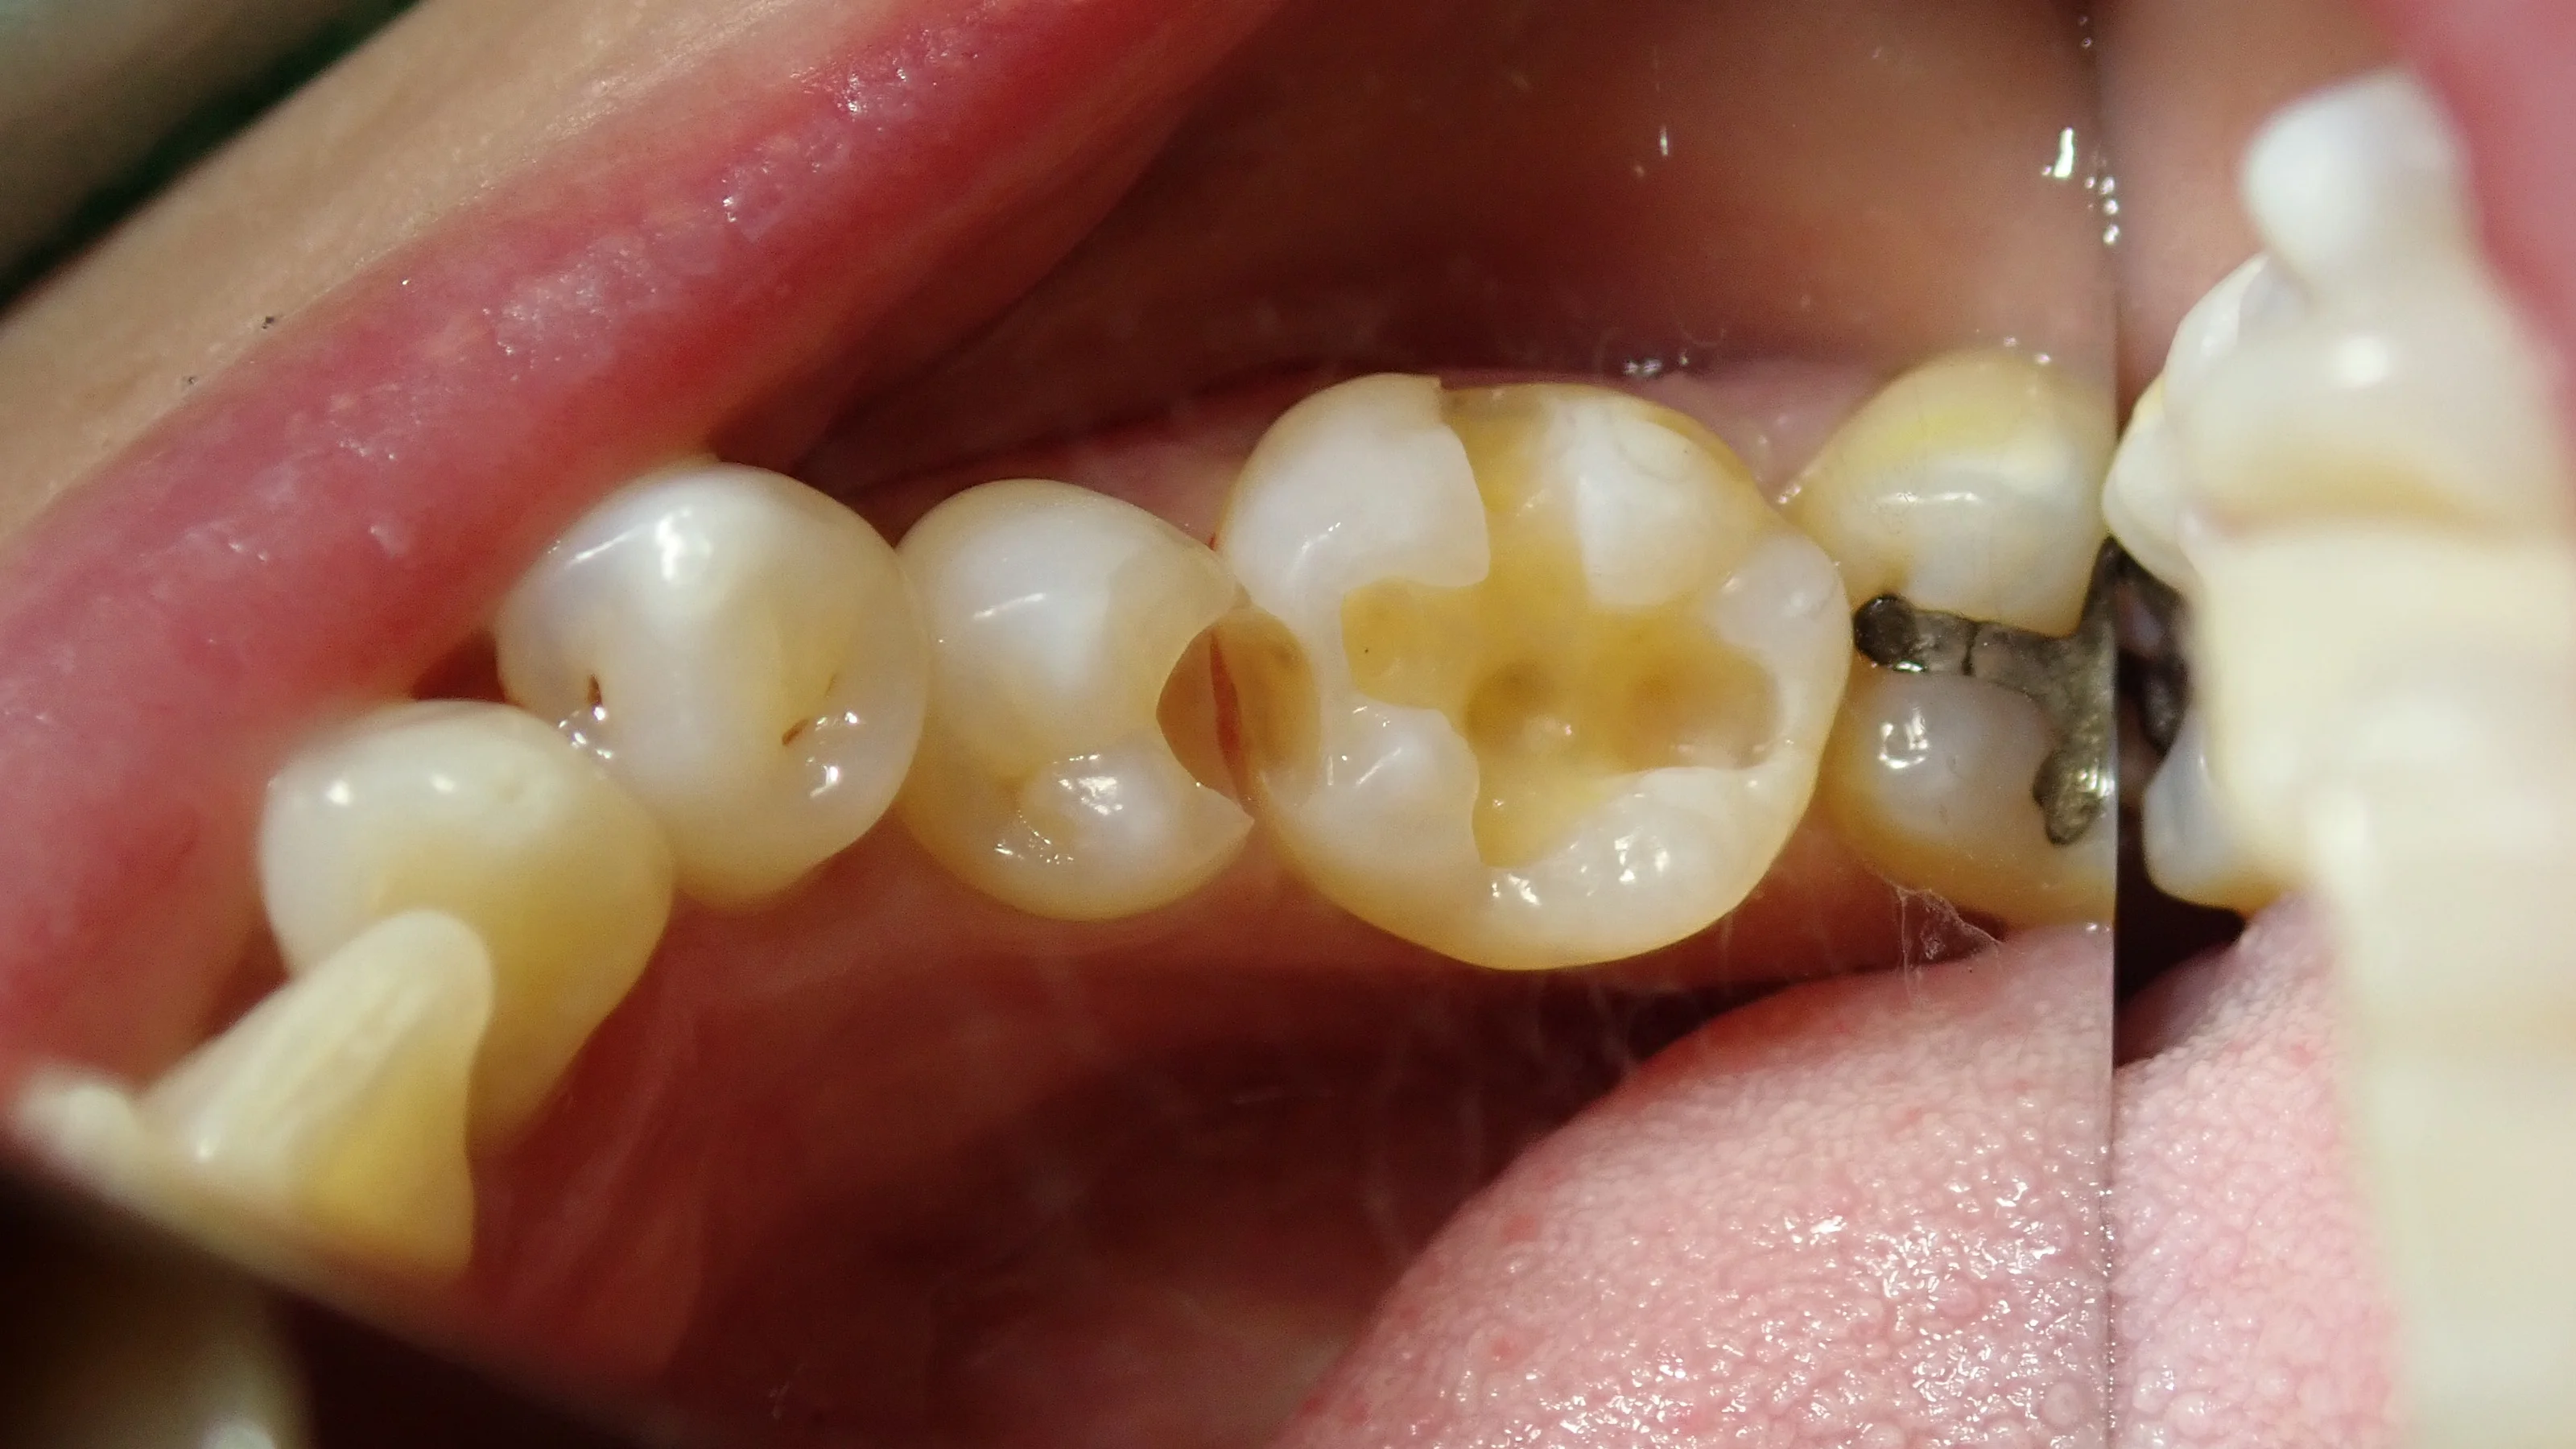

詰め物をどちらも除去したのがこちら。

結構黒いのが見えてきたと思います。

手前の、白い詰め物は外していない状況で撮っちゃいましたね。すみません。